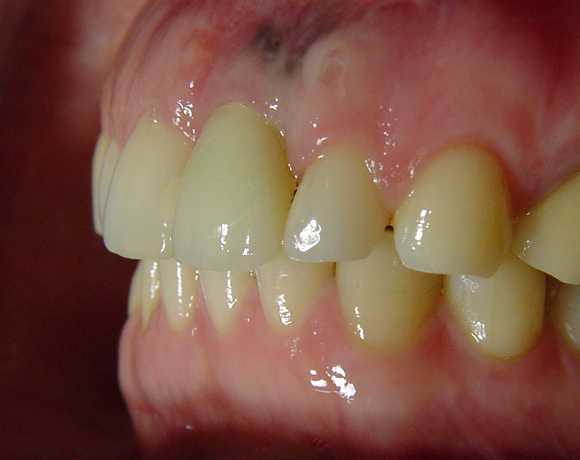

Bei dem letzten Patientenfall lagen Nichtanlagen der Zähne 12, 24, 34, 35, 44, 45 vor. Bei Zahn 12 schimmert das Implantat durch, es war sehr wenig Knochen vorhanden, aber das Ergebnis ist seit acht Jahren konstant gut. Zahn 22 lag als Zapfenzahn vor und wurde mit einem Veneer versorgt.